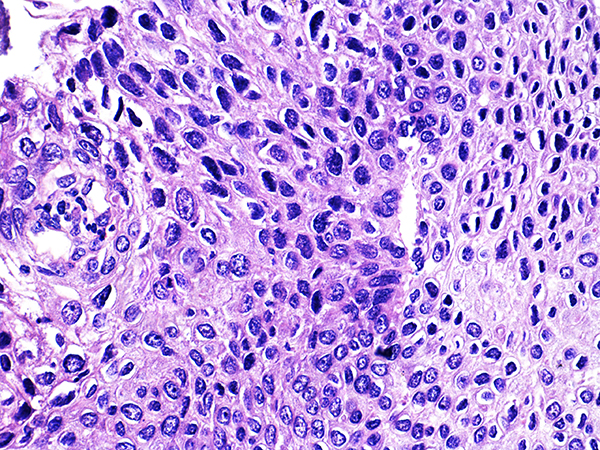

Case 3

Soft Bx CIN 2-3 10x - Low Power

![]() Case 3

Soft Bx CIN 3

10x - Low Power |